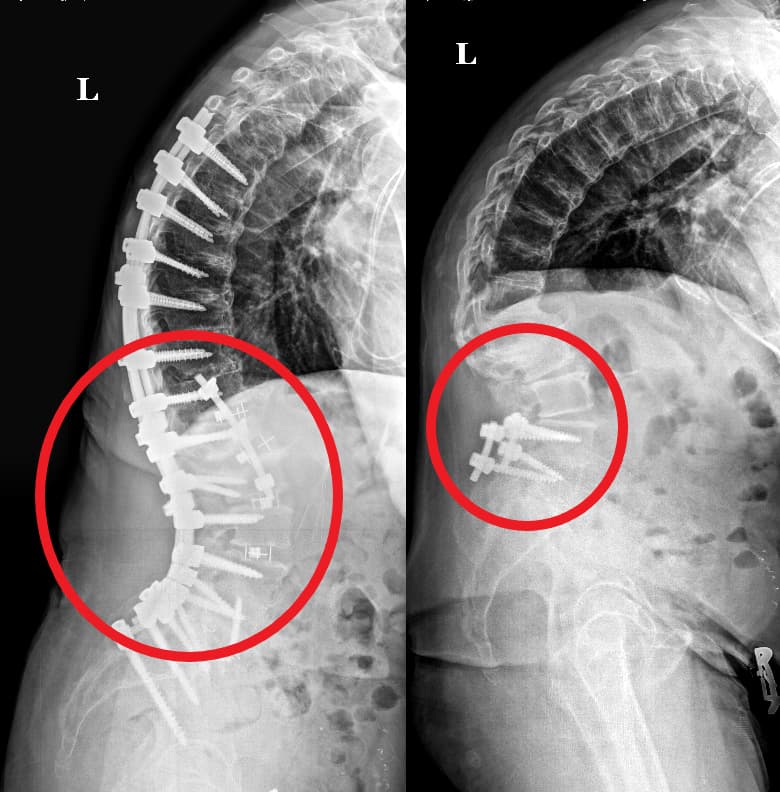

- Hardware Failure: Screws, rods, or other implants used in the initial surgery may loosen, break, or shift.